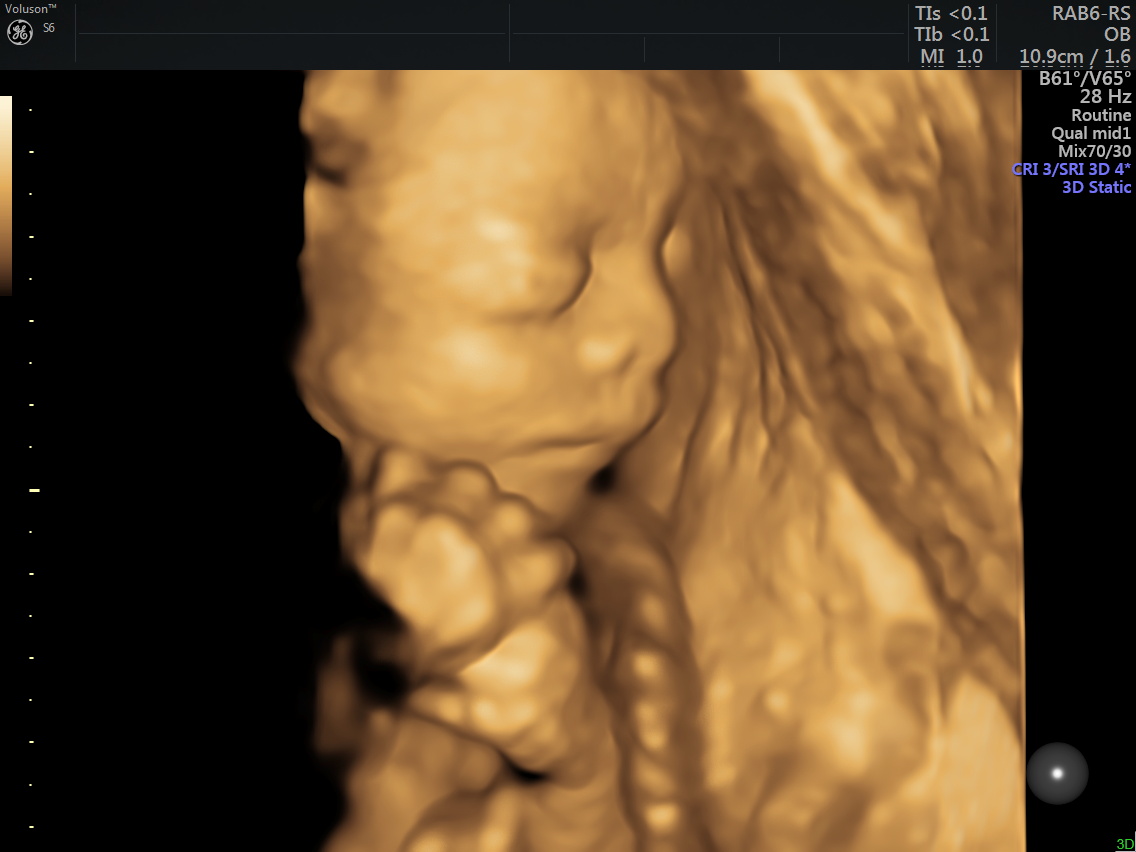

4D (dört boyutlu), Renkli, Ayrıntılı Gebelik Ultrasonu

4 boyutlu renkli ultrason ve 3 boyutlu ultrason aslında aynı anlama gelmemesine rağmen halk arasında , ayrıntılı ultrason, detaylı ultrason , ileri düzey ultrason, anomali ultrasonu , 2. basamak ultrason, ikinci düzey ultrason, renkli ultrason , büyük ultrason , genetik ultrason ile aynı anlamda kullanılmaktadır.

Anne adayı 4D Renkli Ultrason Sayesinde Bebeğine Daha Kolay Bağlanabilir.

4 boyutlu renkli ultrason cihazı ile çok erken dönemde cinsiyet, yarık dudak, yarık damak, eksik parmak, beyin ve omurilikten kaynaklanan rahatsızlıkların erken tanısı konulabiliyor.